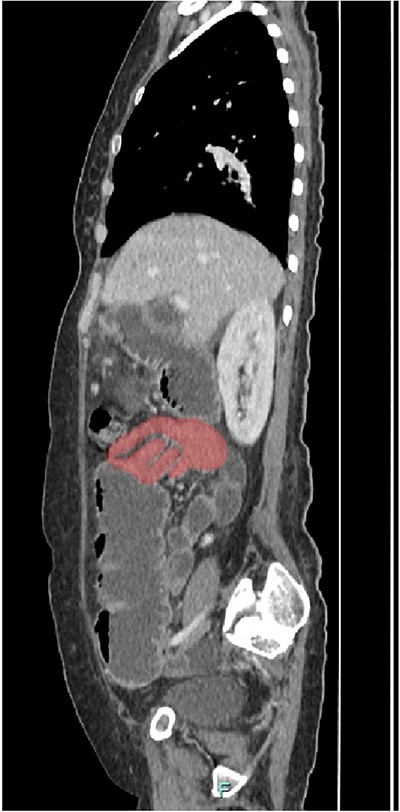

Her abdominal x-ray showed a dilated small bowel with a most likely transition point at the ileum and a collapsed large bowel (Fig. 1). Computed tomography (CT) of the abdomen showed an intussusception with the transition point at the proximal ileum with mesenteric invagination (Figs. 2 and 3).

Coronal view of CT scan. Intussusception transition point is seen likely at the proximal ileum with evidence of ‘bowel in bowel’ appearance, measuring ~7.8 cm.